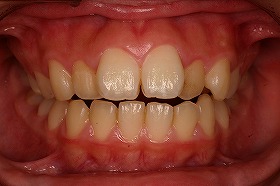

歯の矯正治療 症例ビフォー&アフター

この症例は、出っ歯を矯正治療でキレイにしたケースです。

しっかり噛んでいなかった前歯がかみ合うように並べました。

最初にいらしたときには、出っ歯であることによって

噛み合わせが上手くいかず、口を閉じることが出来ないケースでした。

東京世田谷矯正歯科センターで、治療を進めると

出っ歯も後ろに下がり、噛み合わせもキレイになりました。

さらに上の歯が下の歯とあたるようになり、

とても食事がしやすくなったと喜んでいました。